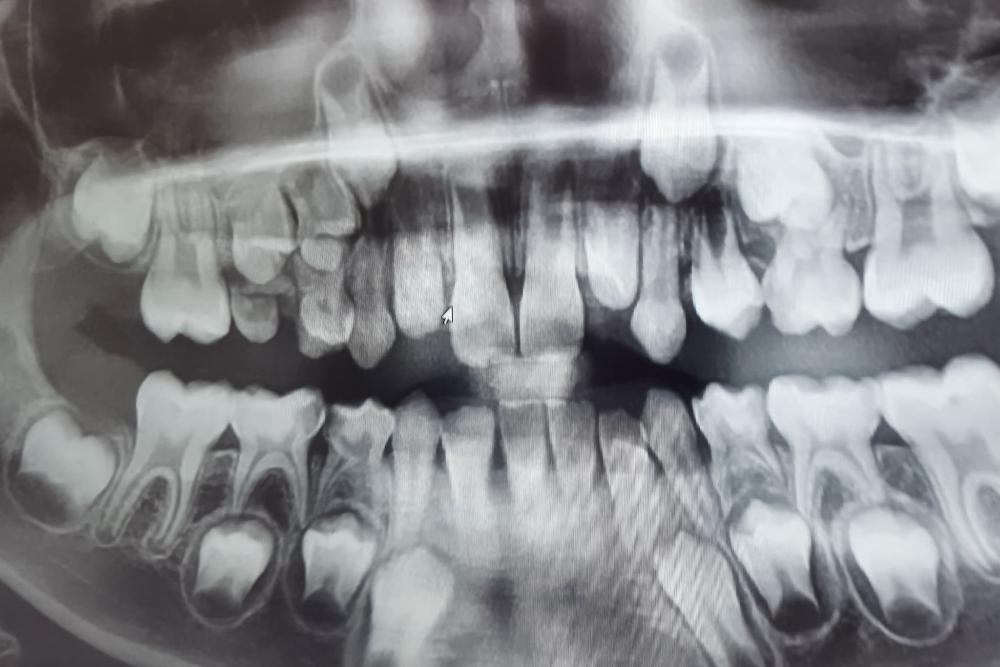

By using digital dental x-rays in our office, we obtain the highest resolution images available. This allows our dentist to accurately analyze the condition of your teeth as well as your periodontal and bone health.

Digital images allow us to zoom in, adjust exposure, and modify the contrast of each image, so our dentist always has the most accurate information about your oral health and can provide you with the best dental care possible.